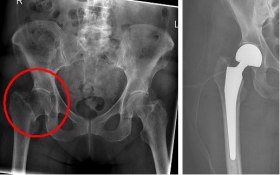

Pertrochanteric fractures, which are not femoral neck fractures close to the hip, are treated with a so-called gamma nail. The rupture here runs through the large and / or small "hillock" (trochanter major and minor) of the thighbone. Here, due to the location of the fracture, the blood supply to the femoral head is NOT compromised. After the operation, an immediate mobilization can take place under pain-adapted full load.

Oberschenkel 5

Picture: In this pertrochanteric femur fracture, a gamma nail was used to stabilize the fracture. The femoral head does not have to be replaced in this case, because the femoral neck is intact and the femoral head is still well supplied with blood.